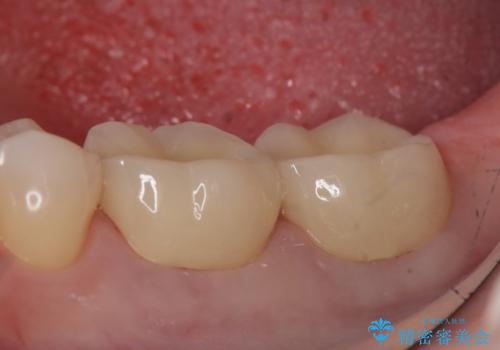

外れそうで不適合のかぶせ物の根管治療からの再治療